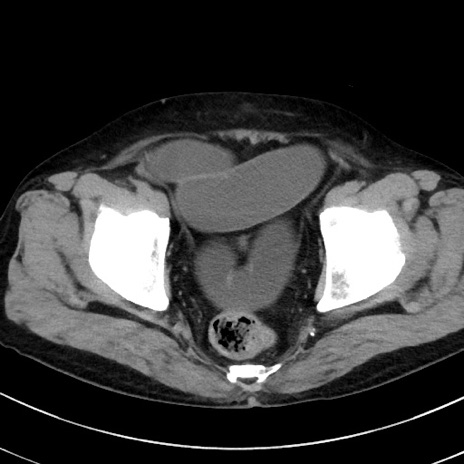

症例38(横断像)

【症例】70歳代 男性

【主訴】腹痛・嘔吐

【現病歴】昨晩より、嘔吐・腹痛あり。今朝になっても嘔吐あり。来院。

【既往歴】心臓バイパス手術、開腹胆摘、腸閉塞

【身体所見】BP 107/71mmHg、HR 116/min、腹部:平坦、軟、下腹部に軽度圧痛あり。反跳痛なし。

【データ】WBC 15100、CRP 0.32